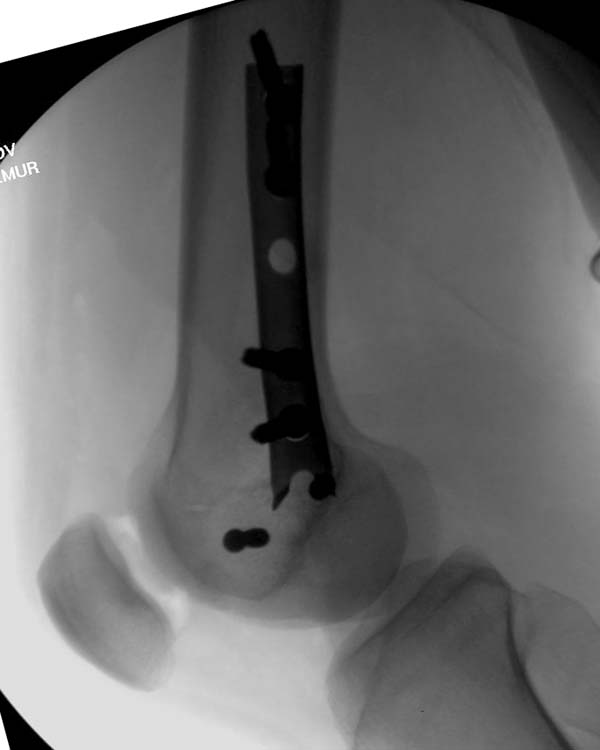

[Ortho] Нелеченный перелом Hoffa

Здесь представлены различные варианты фиксации перелома, а также снимки

комбинации перелома с повреждением хряща (12-19). Пластика хряща

OsseoFit и установка custom made plate.